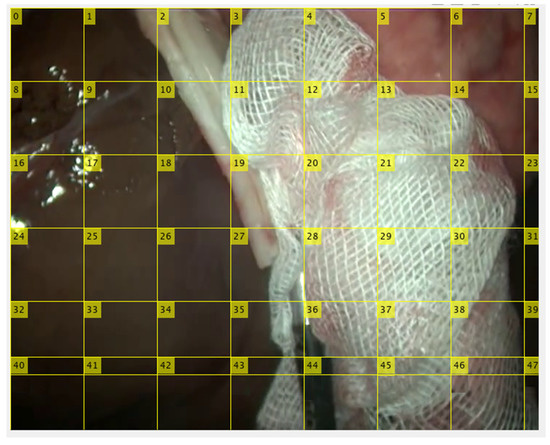

3.3. Gauze Segmentation